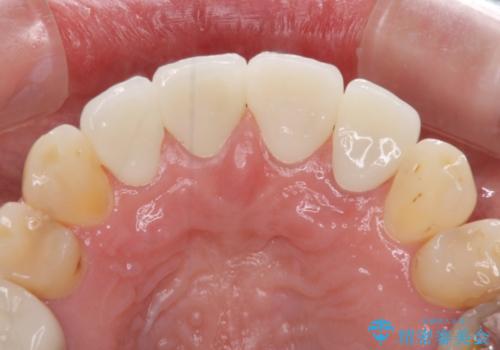

- 前歯の虫歯や治療跡が気になるとのことで来院された患者様です。

以前矯正治療をされ、その時には歯列が整ったので満足されたそうですが、若干の後戻りにより隙間ができ、矯正治療前に治療していた虫歯の跡が気になったため、オールセラミックによる審美治療を希望されました。

目立つ範囲である前歯4歯をオールセラミッククラウンにて補綴することとしました。